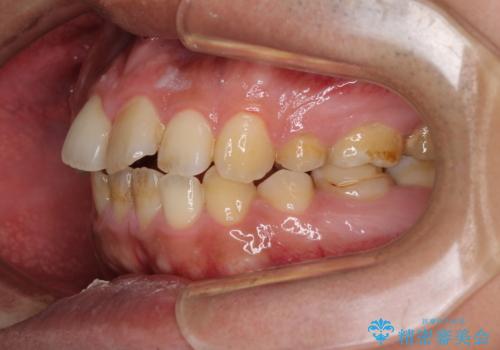

後戻りでデコボコの前歯 インビザライン矯正治療

- 高校時代に行った抜歯矯正が後戻りをしたとのことで来院された患者様です。

再矯正であることから、目立ちにくい装置を希望されたため、インビザラインにて矯正治療を行うこととしました。

下顎骨が左側に変位しているため、正中が合わないことは予想できましたが、歯列が整った後も咬み合わせが安定せず、咬み合わせを落ち着かせるために1年以上の期間を要しました。

噛みにくさの改善に時間がかかってしまうことがインビザラインの欠点の1つといえます。